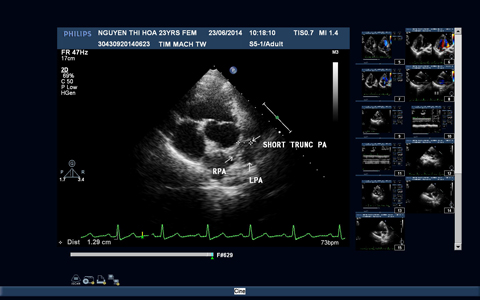

Hình 3: Hình ảnh siêu âm tim trước và sau phẫu thuật

3A: Mặt cắt trục ngang cạnh ức trái cho hình ảnh động mạch phổi chỉ có một phần hội lưu và hai nhánh động mạch phổi.